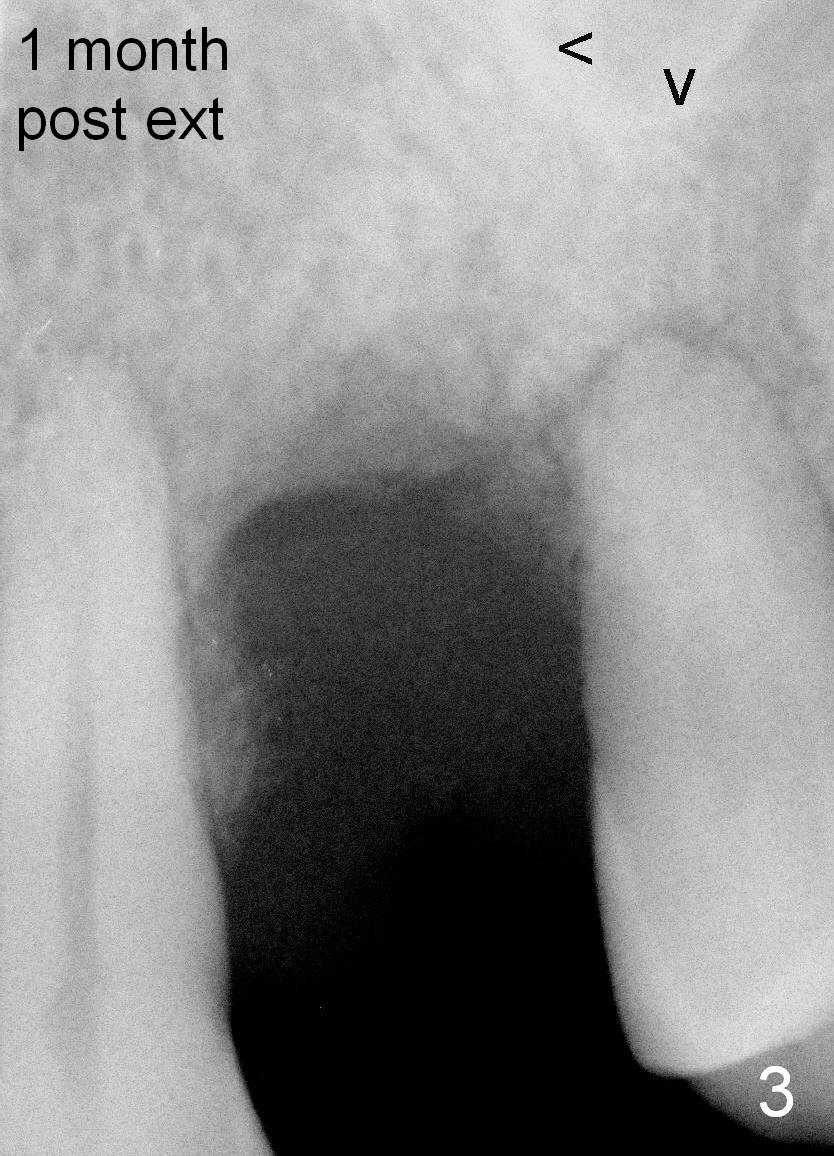

Fig.3,7,10-14 (at the same magnification) show regrowth of crestal bone around the implant postop.

Fig.3: #12 was extracted a month ago, arrowheads: sinus floor.